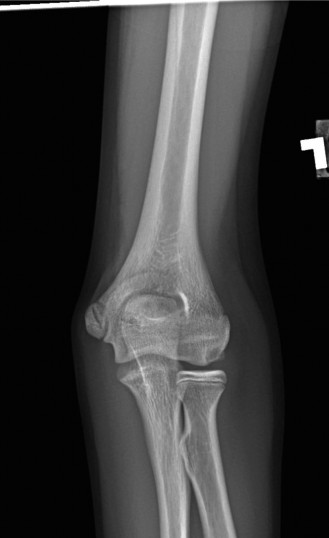

A 23-year-old, semi-professional football linebacker presents with left elbow pain after a game. He extended …

A 14-year-old baseball pitcher presents to the office with left throwing elbow pain for the past two months w…